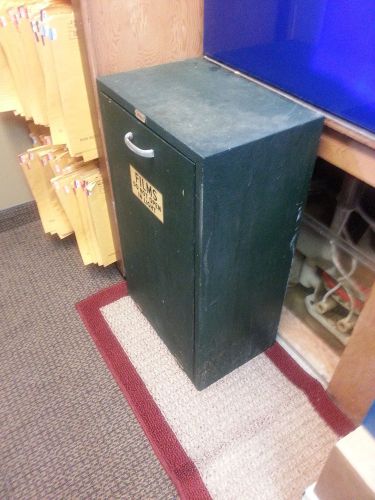

Black, light-safe X-ray film bins

X-Ray Film box for a dark room